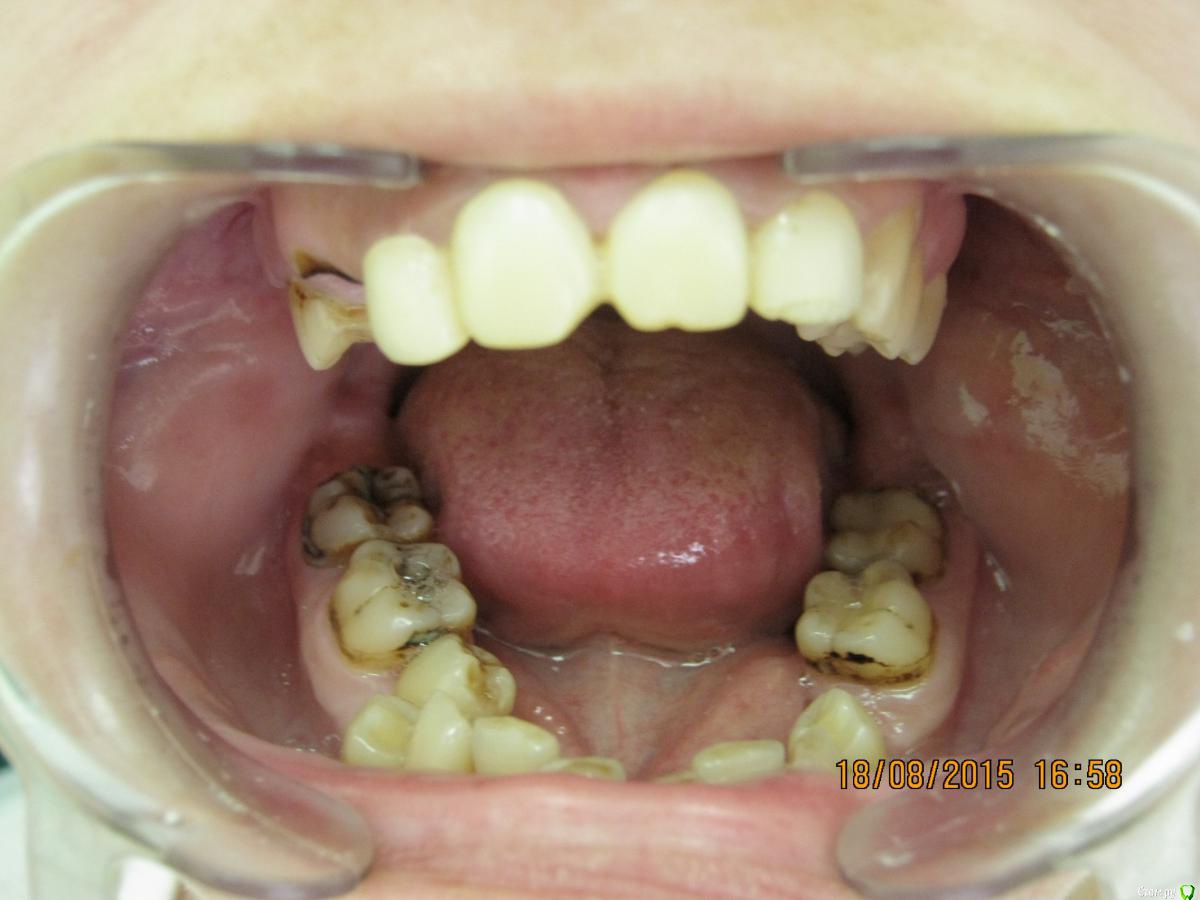

SeregaStomatolog Опубликовано 18 августа, 2015 Поделиться Опубликовано 18 августа, 2015 Добрый вечер уважаемые коллеги!В клинику обратилась пациентка с такой ситуацией во рту.Подскажите пожалуйста что можно сделать и с чего начать. Ссылка на комментарий

krokomot Опубликовано 18 августа, 2015 Поделиться Опубликовано 18 августа, 2015 Бюджет не очень большой,в пределах 50-70 т.р для такого рода патологии как-то уж совсем мало, тут еле в съемники с пару коронками влезешь. Налицо вторичные деформации, десневая улыбка у пациентки и проблемы с периодонтом*, весь букет)) А что хочет пациентка?, уж не голивуд ли?)) Ссылка на комментарий

SeregaStomatolog Опубликовано 18 августа, 2015 Автор Поделиться Опубликовано 18 августа, 2015 Во-первых она хочет нормально улыбаться,не стесняясь отсутствующего клыка.Во-вторых она хочет нормально жевать,т.к. отсутствие 1.7,1.6 не позволяет это делать.Я сразу сказал пациентке что вариантов без ортодонтии мало (если они вообще есть) и обещать ничего не стал.Случай сложный,поэтому хочется узнать в принципе,на будущее,какие варианты лечения возможны (если можно по подробнее).Пока что я снял слепки,отлил модели-пошел за советом к коллегам в другую клинику-все настаивают на ортодонтии.Теперь вся надежда на Вас коллеги,подскажите что можно придумать более менее приемлемое без ортодонтии. Ссылка на комментарий

SeregaStomatolog Опубликовано 18 августа, 2015 Автор Поделиться Опубликовано 18 августа, 2015 Сделав как хочет пациентка вы не получите красивый результат, которого она ждет! и получится что вы не смогли реализовать ее мечты , а значит доктор неахти)) да и вы не особо результатом будете довольны, вам это надо? Если в эстетике проблем нет, восстановите функцию. Ненужное удалить, длинные зубы дэпульпировать, укоротить ну и коронуйте))Мне кажется если я возьмусь,то все равно не буду результатом доволен,т.к. все реализовать не получится.Самая большая проблема в области отсутствующих 1.6,1.7-зубо-альвеолярное удлинение 4.6,4.7 настолько велико,что они практически касаются слизистой в области 1.6,1.7. Ссылка на комментарий